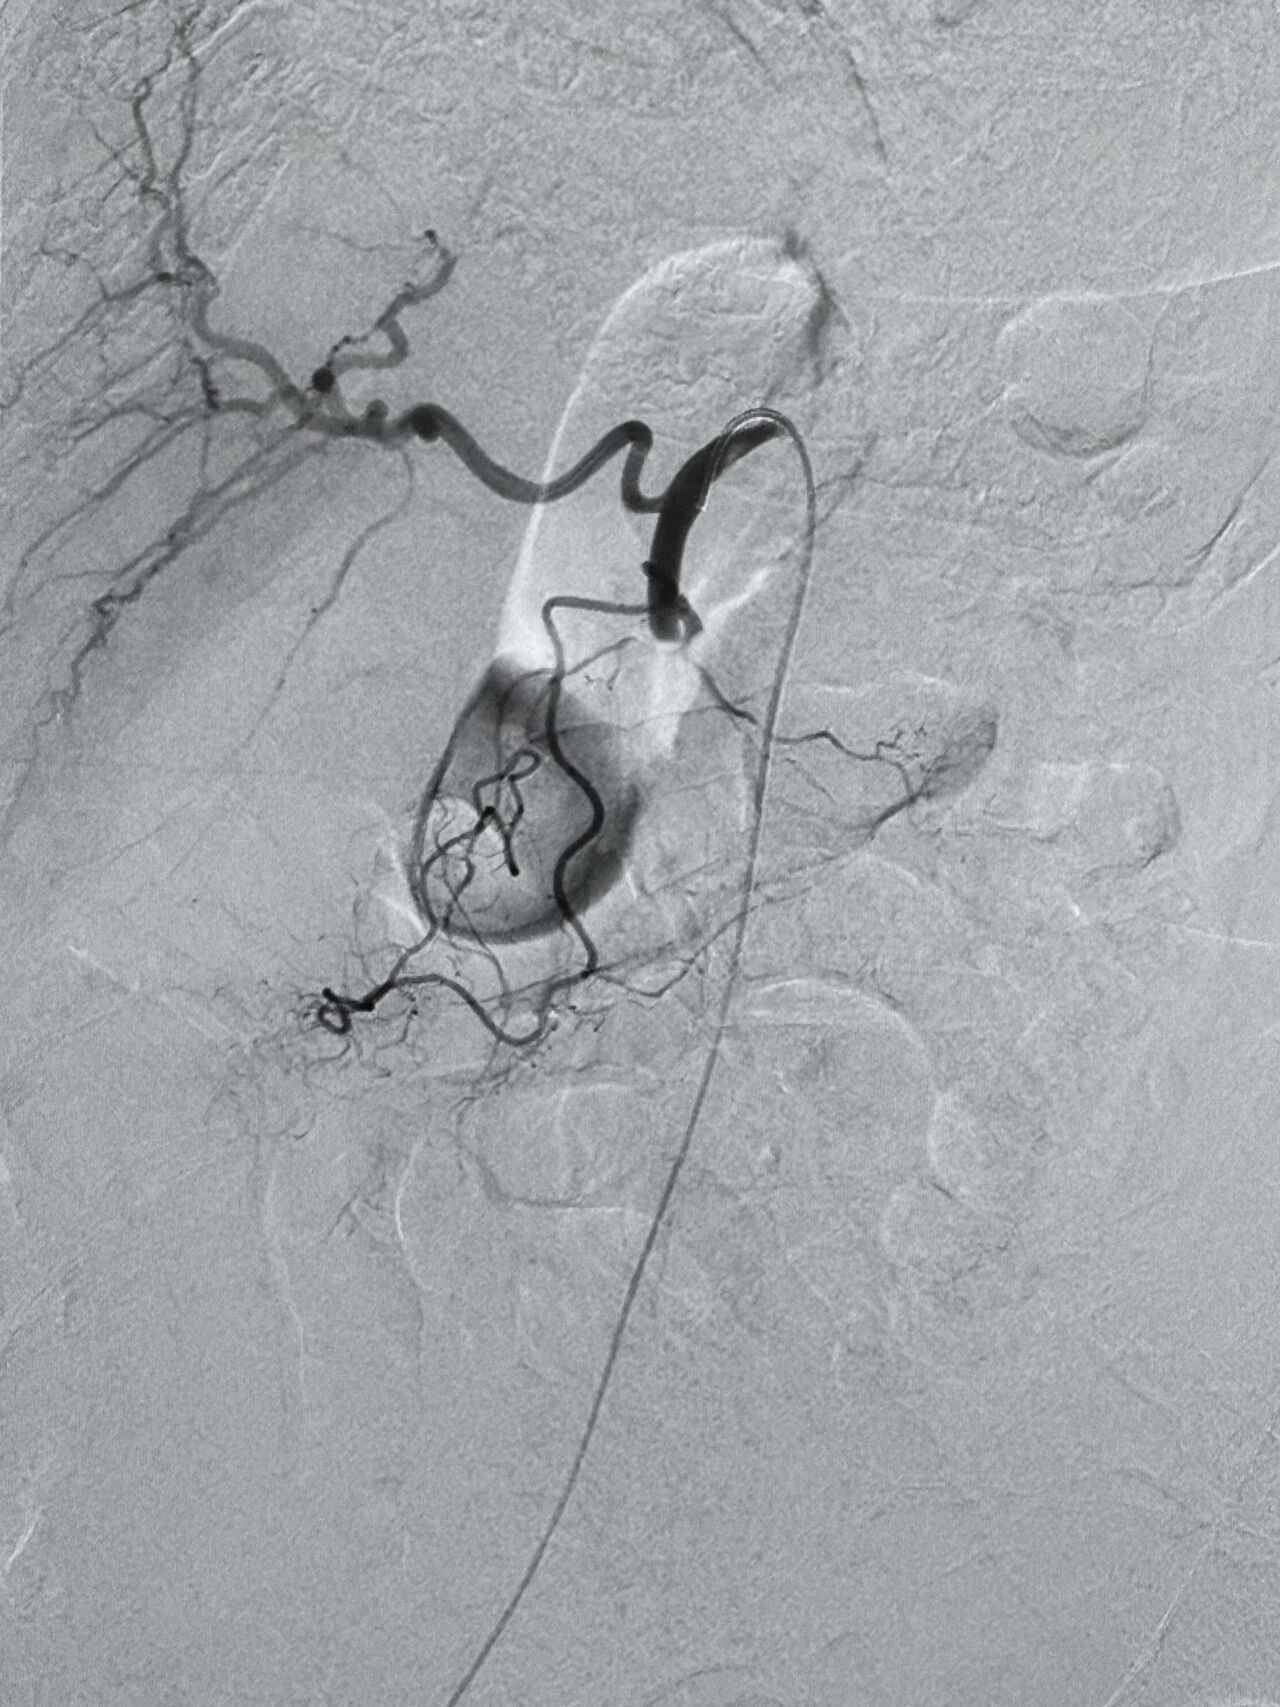

”Revascularization of the superior mesenteric artery (SMA) in a patient with acute mesenteric ischemia.

After achieving recanalization, an additional 200,000 Ui bolus of urokinase was administered.

The final angiographic control demonstrated complete recanalization of the previously occluded artery, with opacification of all colic and jejunal vascular branches.

The patient then continued with an infusion of urokinase at a rate of 120,000 IU per hour.

Pre and post-treatment DSA are shown.